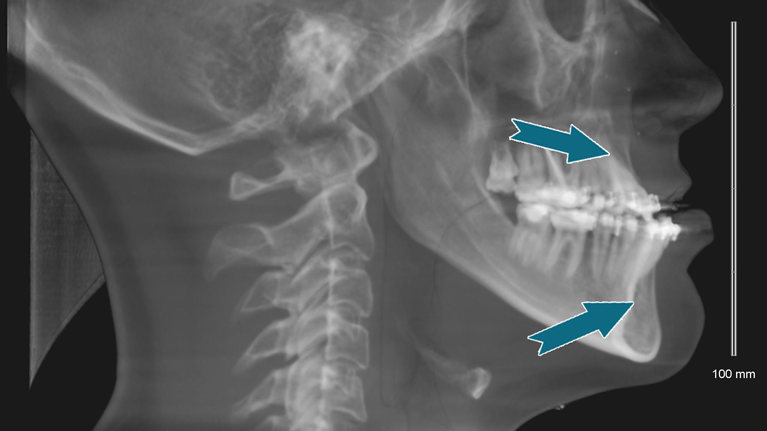

Krogene er placeret i knoglen og stikker ud gennem slimhinden. Den ene krog er placeret over dine fortænder i overkæben og den anden i underkæben under fortænderne. Krogene fungerer som fæste til elastikker, der sættes på cirka 1 uge efter operationen.